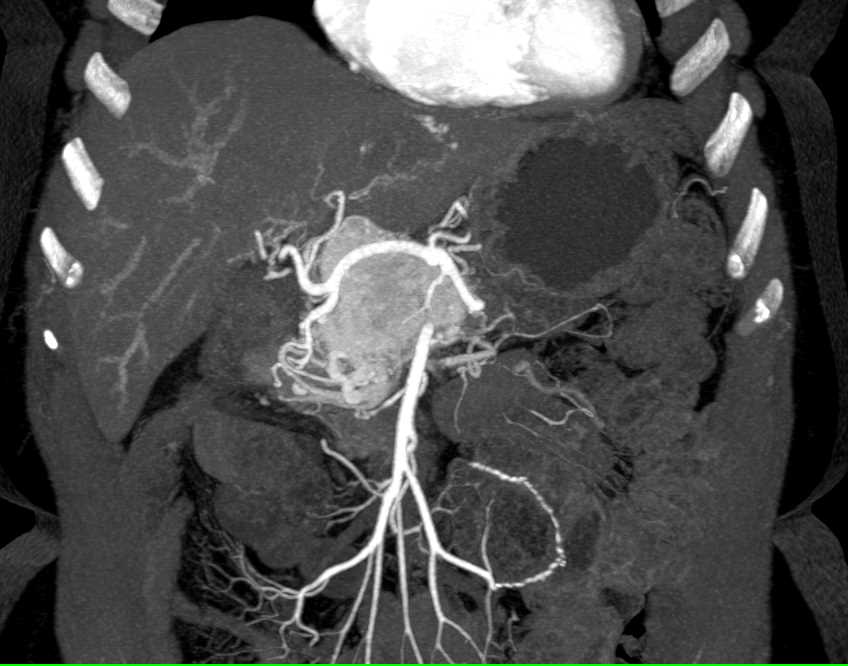

Pancreatic Adenocarcinoma with Arterial and Venous Encasement